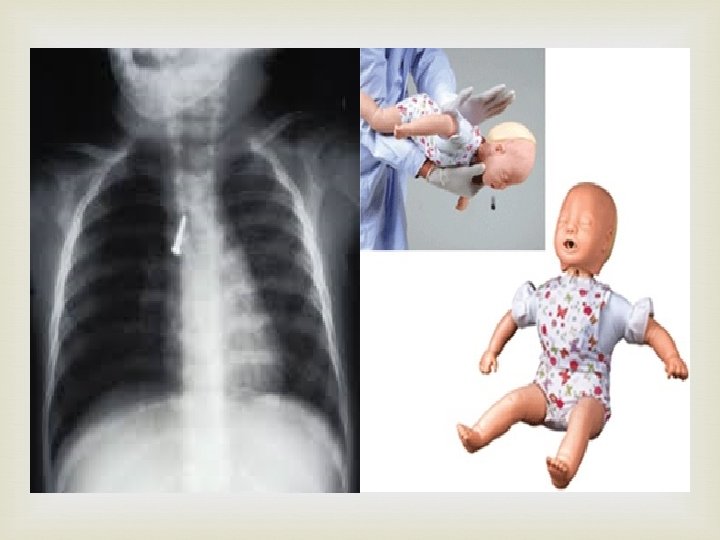

Inhaled Foreign Bodies Inhalation of foreign bodies into the lower respiratory tract is common, especially in children. Pins, screws, nuts, bolts, peanuts, and parts of chicken bones and toys have all found their way into the bronchi. Parts of teeth may be inhaled while a patient is under anesthesia during a difficult dental extraction. Because the right bronchus is the wider and more direct continuation of the trachea , foreign bodies tend to enter the right instead of the left bronchus. From there, they usually pass into the middle or lower lobe bronchi.